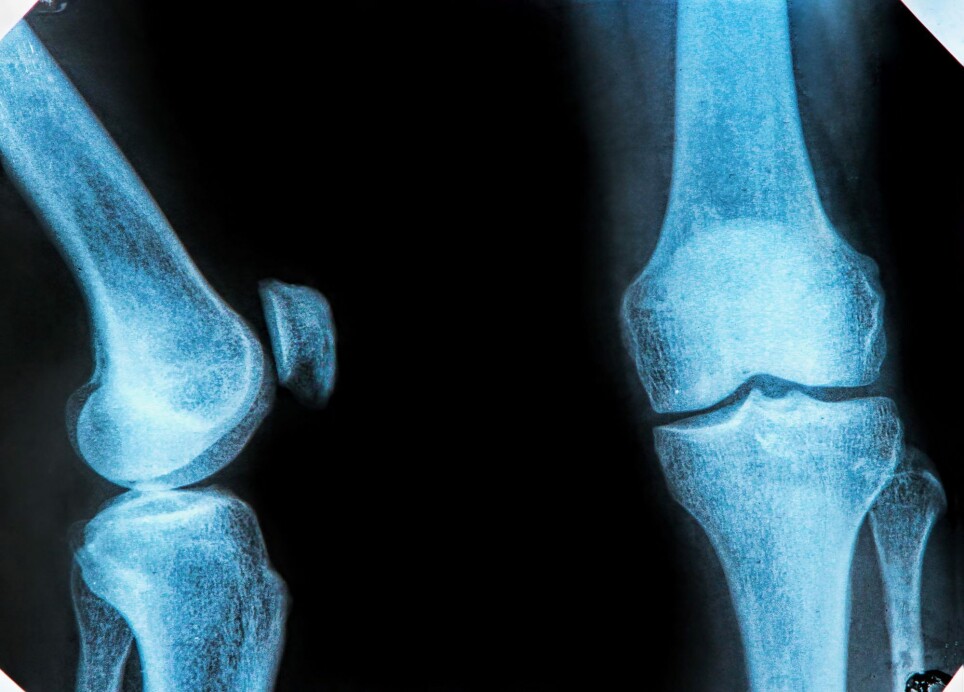

Osteoarthritis is the leading cause of pain and disability worldwide.

There is no cure, only pain relief. Patients’ joints become inflamed, and they feel creaky and stiff in the morning.

The researchers also found special risk factors that exist for women and for weight-bearing joints like our knees.